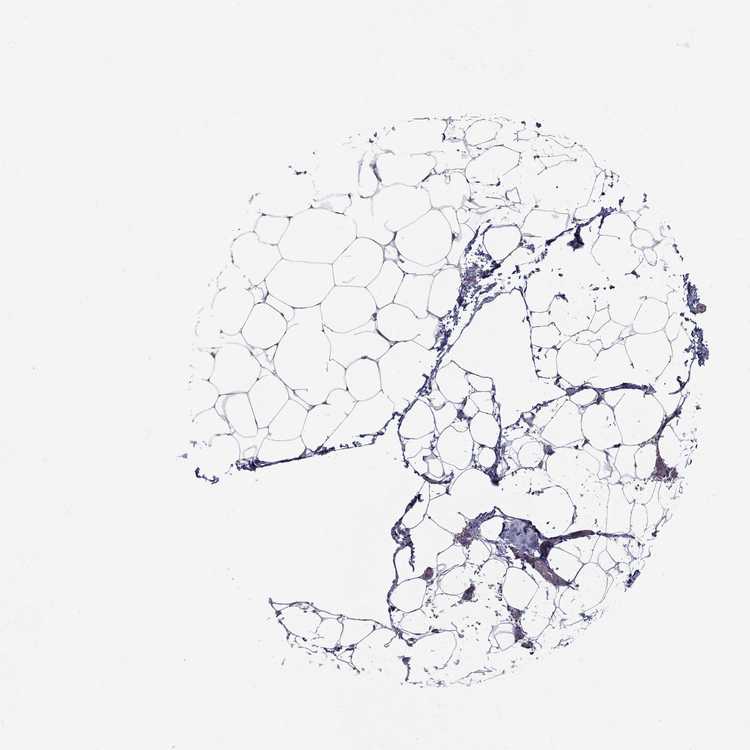

ADIPOSE TISSUE - Antibody stainingi

Antibody staining in the annotated cell types in the current human tissue is reported as not detected, low, medium, or high, based on conventional immunohistochemistry profiling in selected tissues. This score is based on the combination of the staining intensity and fraction of stained cells.

Each image is clickable and will lead to virtual microscopy that enables deeper exploration of all samples and also displays staining intensity scores, fraction scores and subcellular localization as well as patient and tissue information for each sample.

Antibody HPA069509Antibody CAB002167

Adipocytes Not detectedNot detected